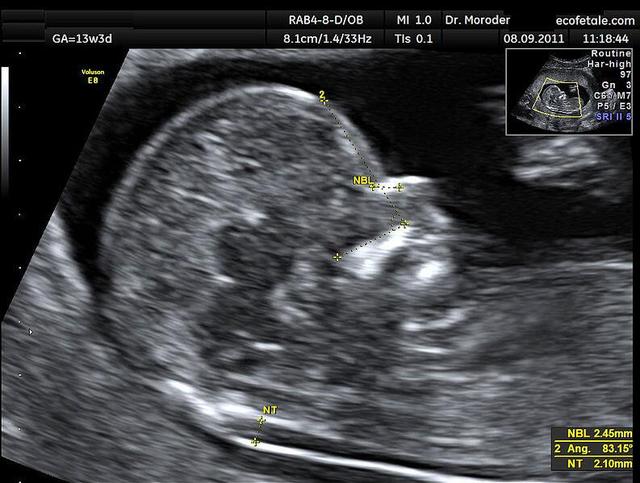

七、正矢位B超图参考

图片来自维基百科的NT超声图

NT是nuchal translucency的简写,翻译成中文是“颈部透明层”的意思,指胎儿颈后皮下组织内液体积聚的厚度。是早期唐氏筛查的重要风险测算项目,也是诊断染色体疾病和心脏问题、其他畸形问题等非染色体问题的重要筛查依据,是整个孕期的大排畸检查中的首次排畸检查。

NT检查的正常值在不同地区不同医院都的标准都会有所差异,奶爸目前所知的就有2.5mm、3.0mm、3.5mm这3个标准。总之,超过正常值,NT越厚,风险就越大。